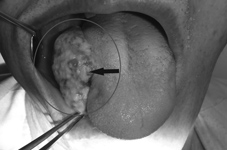

舌部第三期癌

在台灣,口腔癌在男女十大癌症發生率、死亡率為第六位,單就男性十大癌症發生率、死亡率排名更前面為第四位,多數為鱗狀細胞癌和疣狀癌,最常發現發生口腔癌的部位為舌側緣、頰黏膜和下顎後臼齒牙齦,通常會有黏膜顏色或表面結構異常、腫塊、潰瘍、粗糙、不平滑或周邊硬結和淋巴結腫大都是其可能會有的表徵。口腔癌分期必須經由病理組織切片檢查證實有惡性腫瘤的特徵,分為有角質化或非角質化之鱗狀細胞癌,口腔癌分為四期,以腫瘤大小、淋巴結有無侵犯轉移和是否有遠端器官轉移來做依據,第一期和第二期都為較初期,治療方式以安全範圍?度及深度距離病灶邊緣至少1.5到2公分為原則施行原發病灶廣泛性切除手術為主。第三期和第四期為較晚期,除廣泛性切除以外,仍要視是否侵犯淋巴結、淋巴管、血管、神經和重要器官或組織來決定後續是否要接受化學治療或放射線治療。